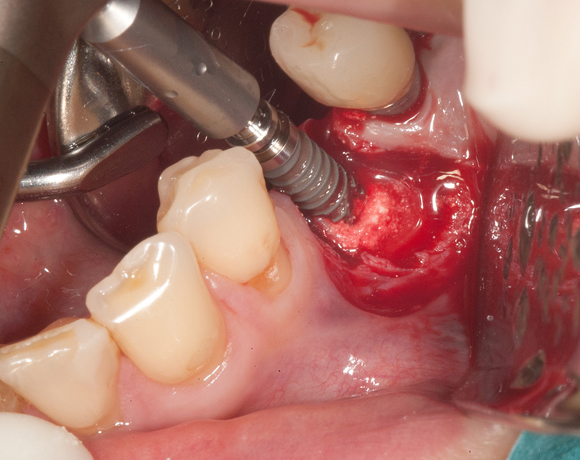

Die Knochenspaltung auch Bonesplitting genannt, ist eine geeignete Möglichkeit im Unterkieferseitenzahnbereich Knochen aufzubauen, um Implanate setzen zu können. Vorraussetzung ist eine ausreichende Knochenhöhe.

Im vorliegenden Fall war zwar eine gut Knochenhöhe vorhanden, jedoch war der Knochen zu schmal,

um Implantate aufzunehmen. Hier bietet es sich an den Knochen zu spalten, bei gleichzeitiger Insertion der Implantate und die freien Zwischenräume mit Kunstknochen aufzufüllen. Die Augmentation wird mit einer Membran abgedeckt. Die Einheilzeit beträgt sechs Monate.